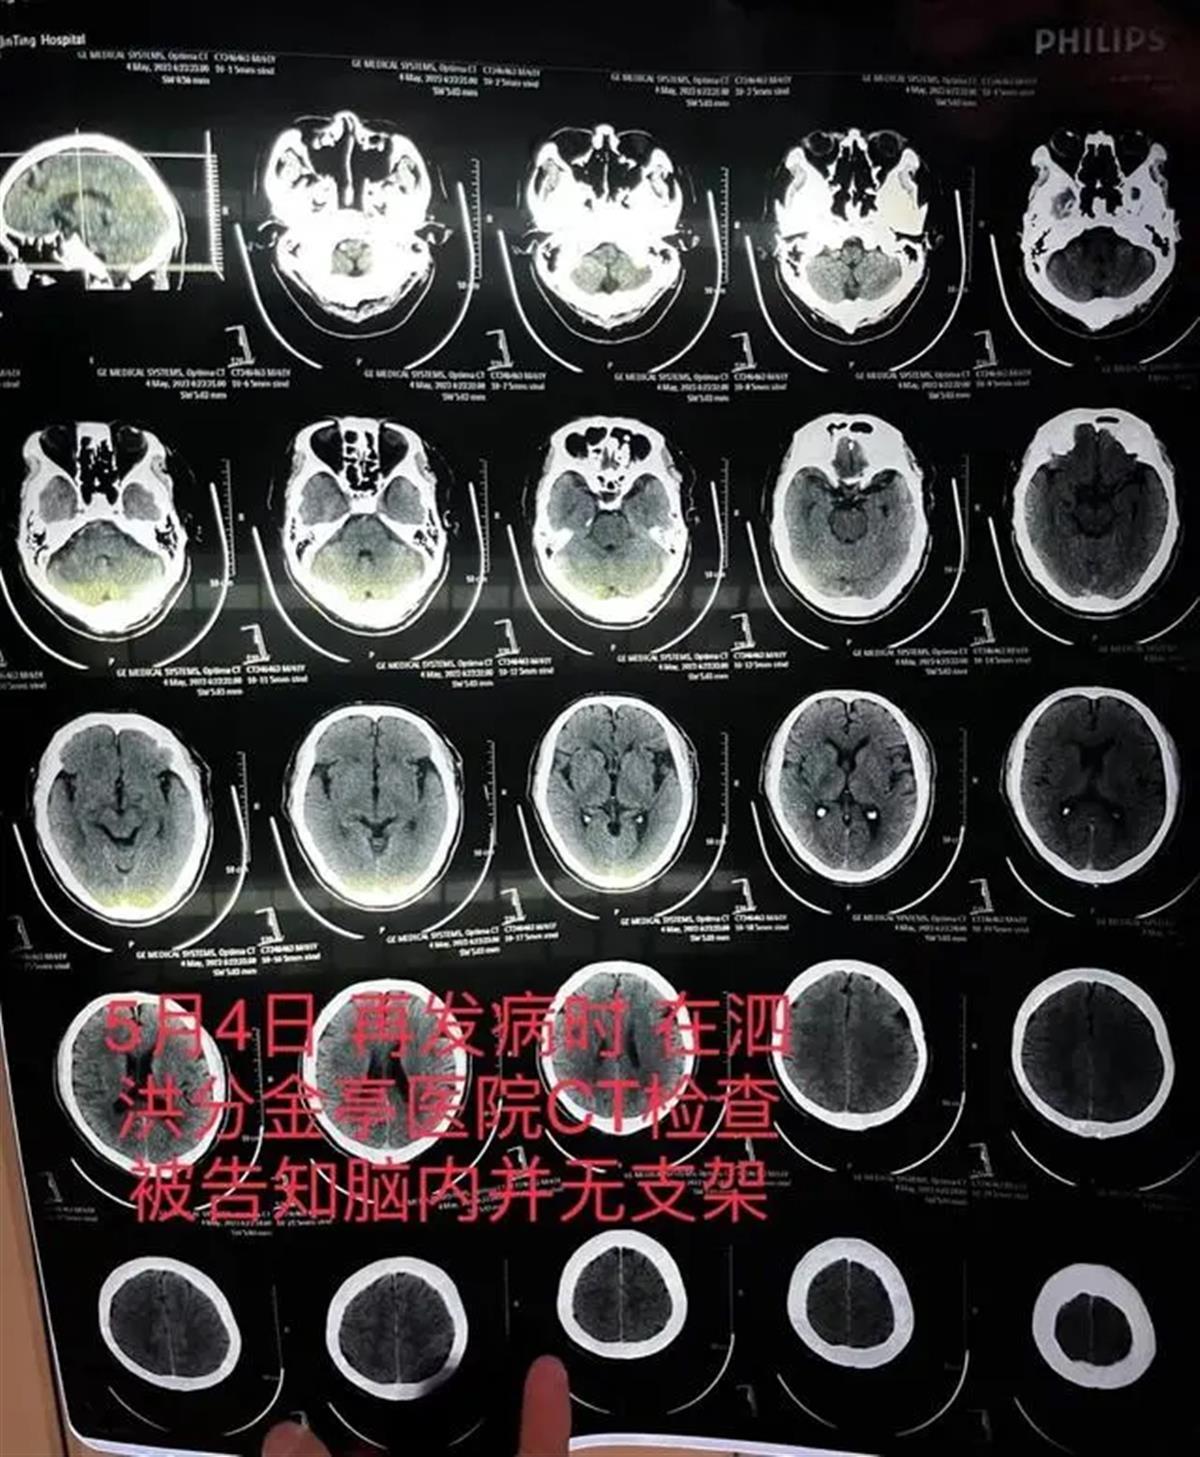

5月4日,朱老汉突发严重脑梗,送医检查发现,其颅内段部分动脉已严重堵闭,同时未发现此前植有支架。朱老汉随后又被转入宿迁第一人民医院,曾作为主刀医生的齐某此时才承认,之前未能在患者颅内血管成功植入支架。6月7日,朱先生父亲因动脉血栓堵闭致大部分脑干坏死,不幸去世。

朱老汉的CT检查报告显示颅内并无支架。(来源:澎湃新闻)